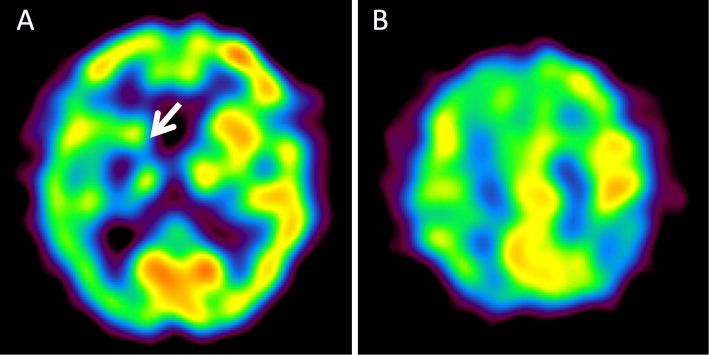

We herein report an 84-year-old woman with right middle cerebral artery (MCA) stenosis who presented with persistent left hemichorea preceding cerebral infarction. She visited our hospital on day 9 after the hemichorea onset. Magnetic resonance imaging (MRI) showed no acute cerebral infarction. Magnetic resonance angiography revealed right MCA stenosis. Her hemichorea persisted for 19 days and subsequently disappeared. On day 21, she developed left hemiplegia. Repeat MRI revealed a cerebral infarction in the right putamen. MCA stenosis can present with persistent hemichorea, even in the absence of cerebral infarction. Persistent hemichorea with MCA stenosis may presage cerebral infarction.

我们在此报告一例右侧大脑中动脉(MCA)狭窄的 84 岁女性患者,其在脑梗死前出现持续的左侧偏侧舞蹈症。她在偏侧舞蹈症发作后第 9 天就诊于我院。磁共振成像(MRI)未见急性脑梗死。磁共振血管造影显示右侧 MCA 狭窄。她的偏侧舞蹈症持续了 19 天,随后消失。第 21 天,她出现左侧偏瘫。重复 MRI 显示右侧壳核脑梗死。MCA 狭窄可表现为持续的偏侧舞蹈症,甚至在没有脑梗死的情况下也是如此。伴有 MCA 狭窄的持续偏侧舞蹈症可能预示着脑梗死。